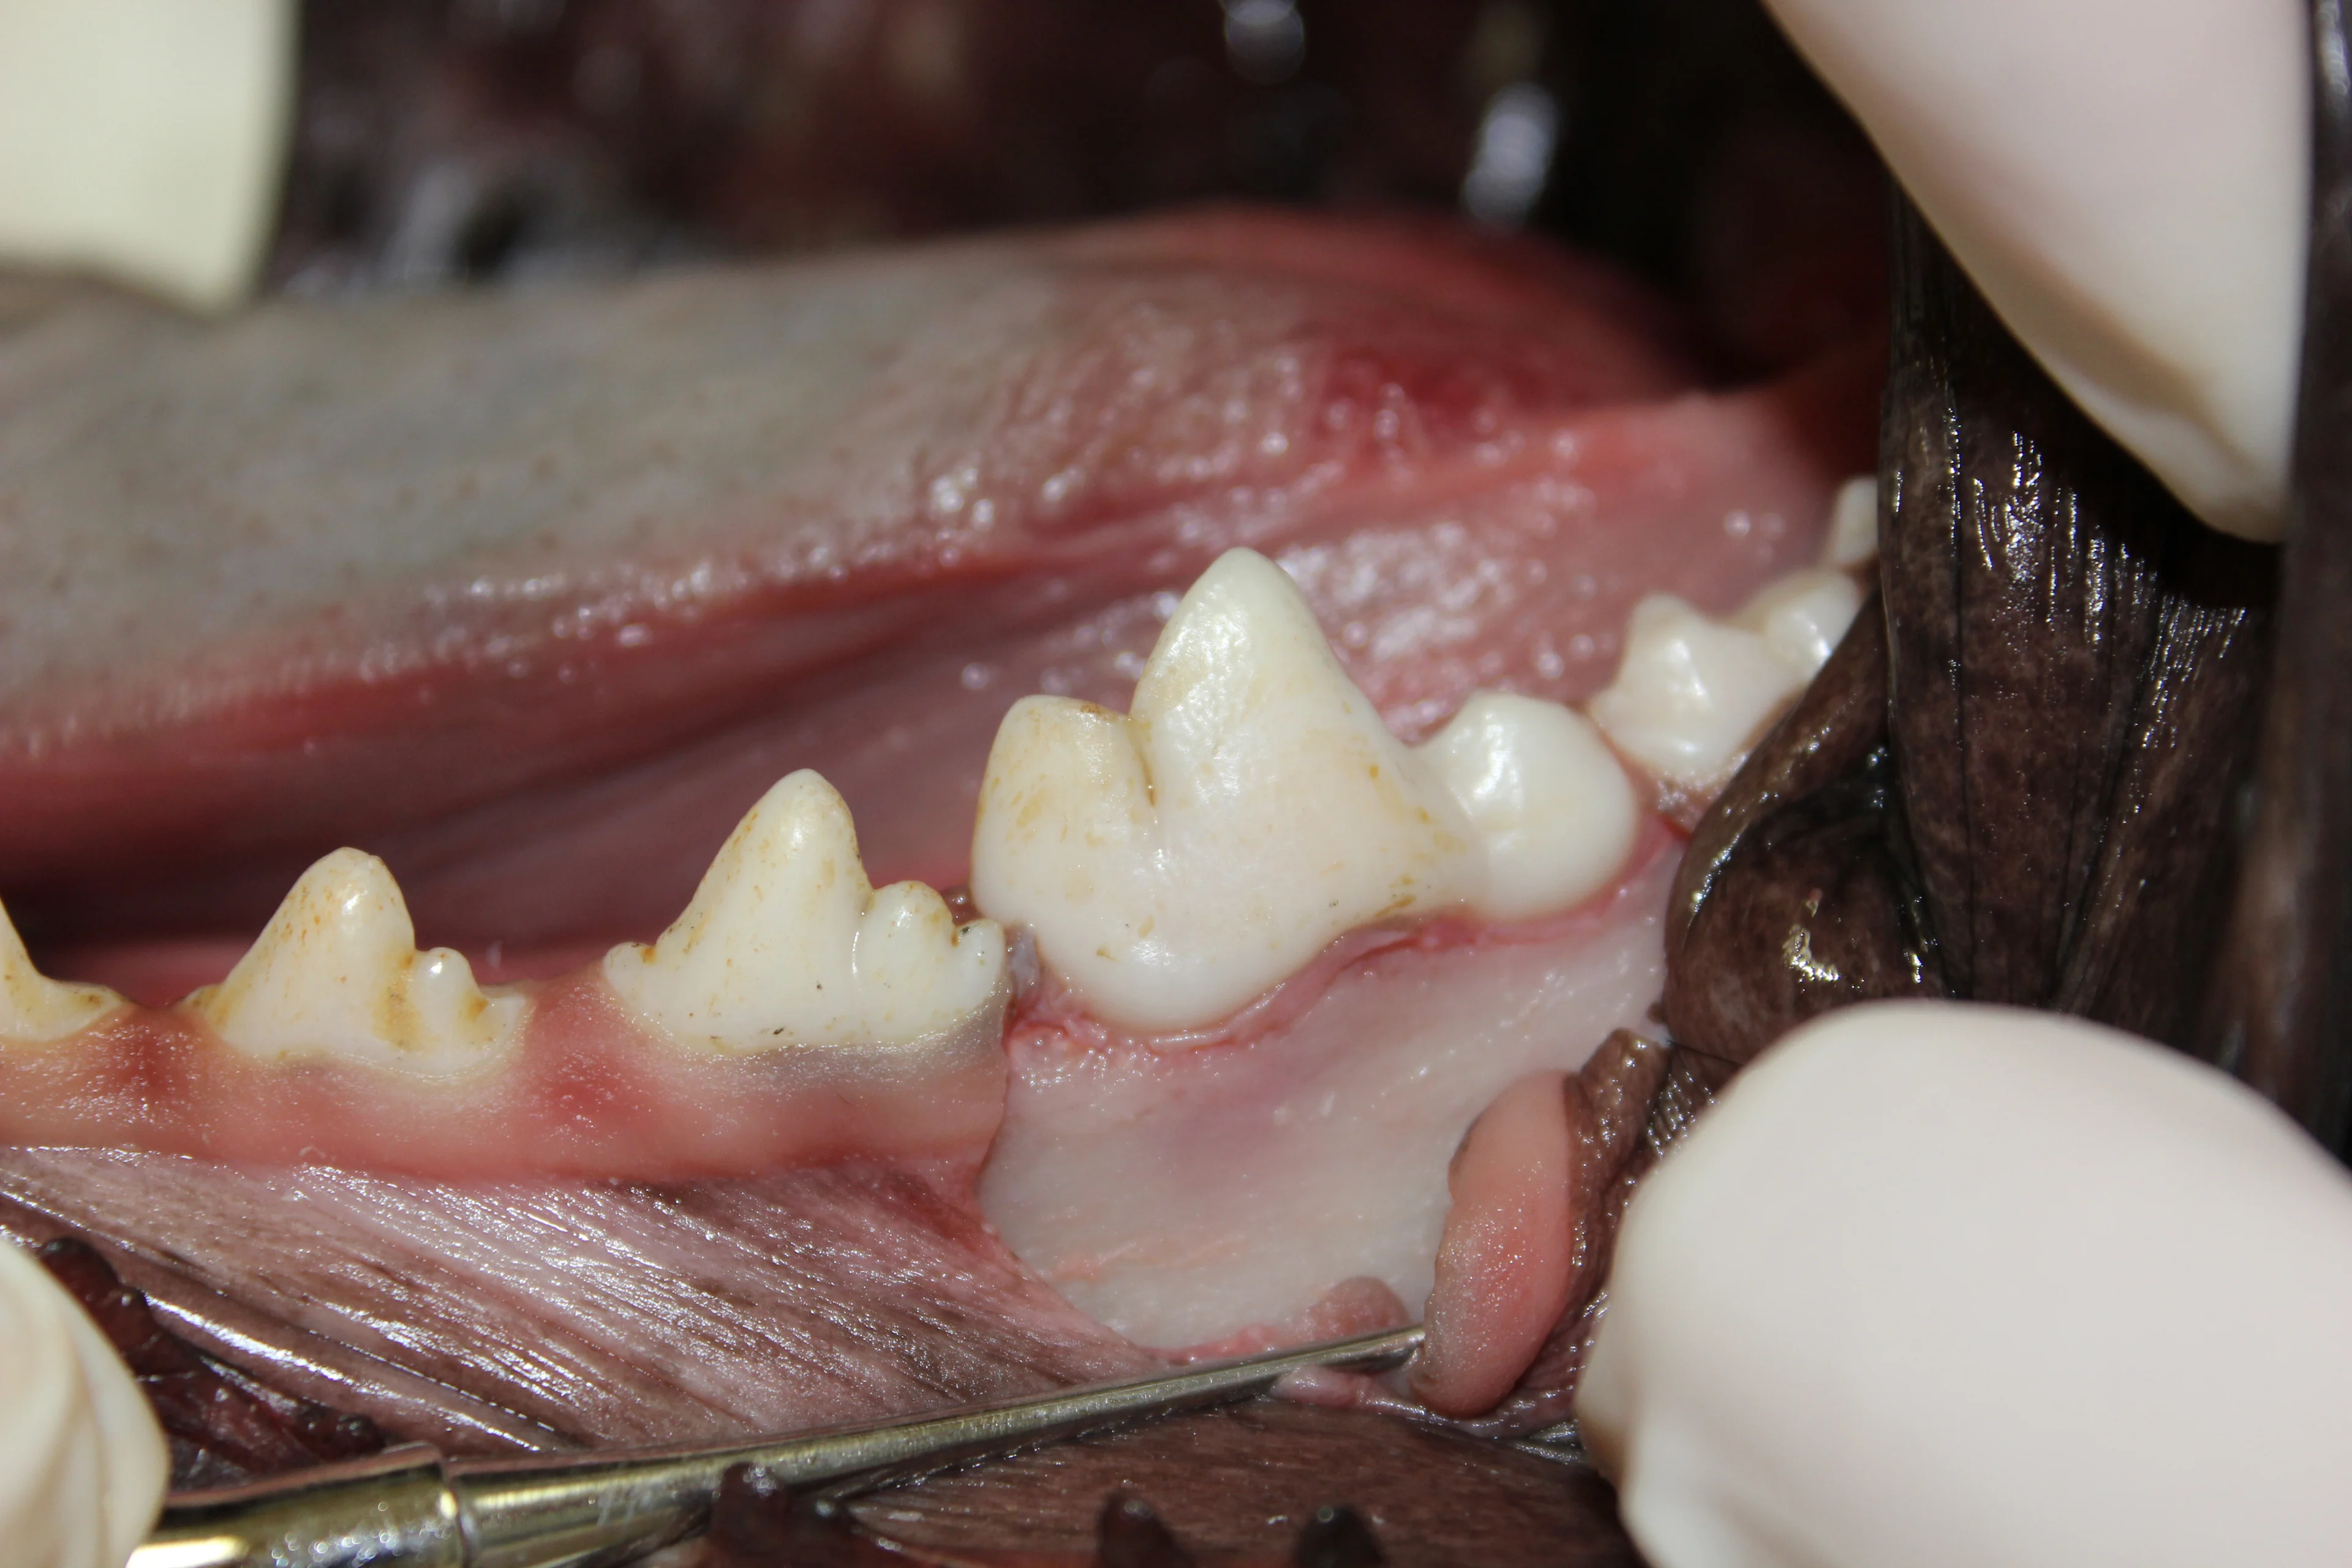

Step 2

(A) Make 2 full-thickness divergent vertical incisions in an apical direction on the mesial and distal edges of the first molar (black lines). Make the incisions through the gingival and alveolar mucosa to create the full-thickness mucoperiostealflap that will be used later to close the extraction site. Incisions may be extended for further bone exposure if necessary. (B) Once both vertical incisions have been made, make an incision into the gingival sulcus connecting the vertical incisions.